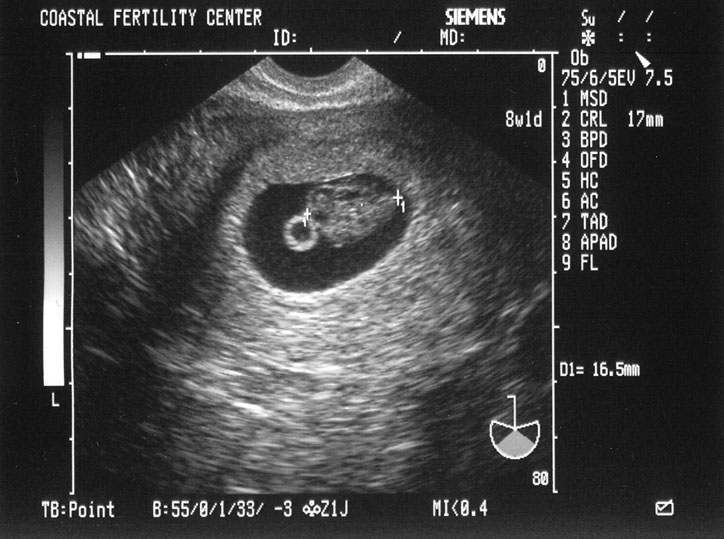

5/10/05 Baby A - 8w1d